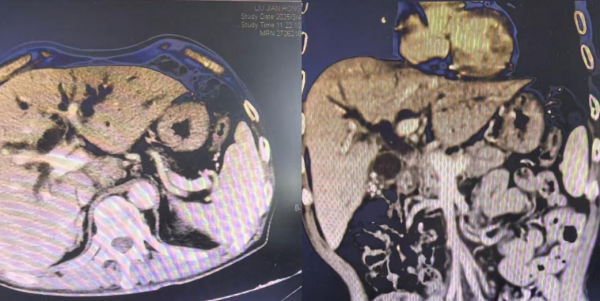

患者胆总管受压,肝内胆管重度扩张

整个手术过程一气呵成,成功开通了梗阻的胆道。手术创口小,患者术后恢复快,全身皮肤及巩膜黄染明显消退,食欲显著好转,精神状态恢复,体重也有所增加,日常生活实现自理。复查CT显示胆道梗阻解除,胆道支架及碘125粒子条位置良好。

胆道支架植入后胆道梗阻解除

胆总管支架术后改变,肝内胆管无明显扩张